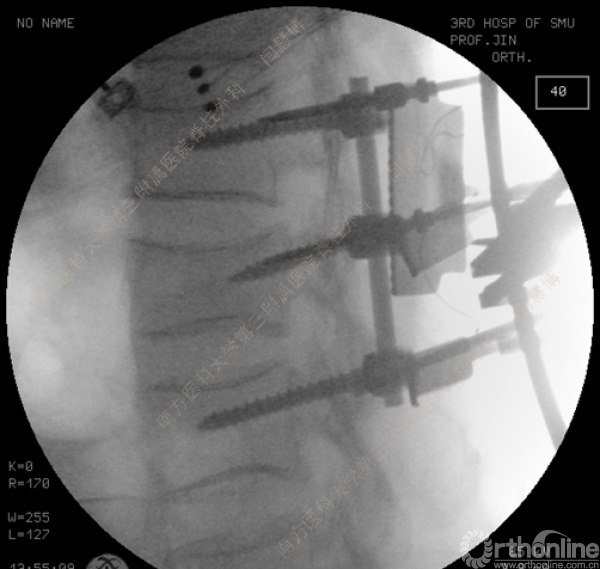

胸腰椎骨折是指由于外力造成胸腰椎骨质连续性的破坏,在如车祸、高处坠落等意外事故中,是最常见的脊柱损伤。老年患者由于本身存在骨质疏松,甚至有可能因为一些如滑倒、跌倒等低暴力因素导致胸腰椎骨折。胸腰椎骨折患者常合并神经功能损伤,且由于致伤因素基本为高能损伤,常合并其他脏器损伤,这为治疗带来了极大的困难和挑战。针对胸腰椎骨折,南方医科大学第三附属医院闫慧博教授介绍了他们运用微创方法治疗的经验。